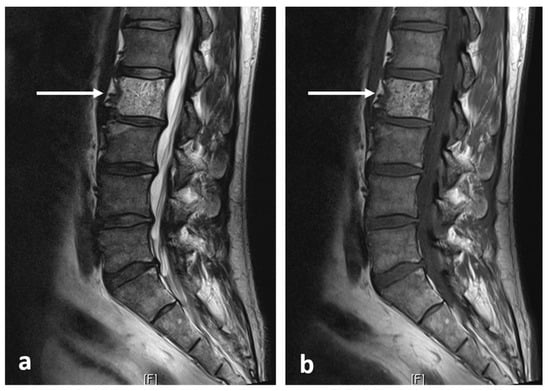

3.7. Haemangioma

| Haemangioma | Honey comb appearance. ‘Corduroy’ and ‘polka dot’ signs. | Usually T1 and T2 hyperintense due to fat content. Signal drop out >20% on out of phase chemical shift imaging. |